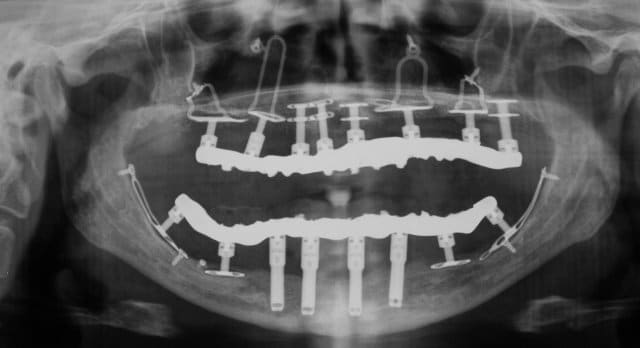

Et pourquoi pas... avec MCI !

Plaques01 1  y5m4zo - Eugenol

Plus la mandibule est fine, plus elle va fléchir. On a observé à maintes reprises une réossification des zones postérieures et de la zone mentonnière avec ré-enfouissement du foramen après quelques mois de mise en charge.

Le diskimplant, de par sa forme et vu la relative étroitesse de son fût 2.3 mm est à même d'accompagner la flexion et s'il ne l'accompagne pas, on peut observer parfois une déminéralisation osseuse autour de certaines partie de disk pour permettre la flexion.

C'est sans conséquence dans la mesure où il ne faut jamais déposer un disk même légèrement mobile s'il n'y a pas douleur ou infection. Avec la reminéralisation de l'ensemble de la mandibule, on a observé une reminéralisation autout des disks.

Pour faire simple: les disks réagissent souvent mieux que les cylindres à la flexion de la mandibule, car ils sont plus souples.

Wow, sympa, il y en a du titane !

Pas d'implants de ce type disponible chez moi...